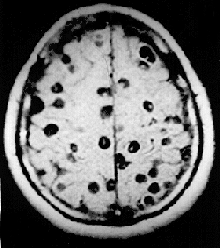

multiple Finnen im Gehirn (MRT-Aufnahme)

Die Zystizerkose (Cysticercose) ist ein Einlagern der Finnenformen des Typs Cysticercus („Blasenwurm“) von Bandwürmern, insbesondere der Cyclophyllidea, in den Geweben eines Zwischenwirts. Prinzipiell können alle Gewebe Zysten enthalten, häufiger sind Unterhaut, Muskulatur, Leber, Bauchfell und Gehirn (dort etwa eine chronisch-lymphozytäre Meningitis oder seröse Meningoenzephalitis verursachend[1]) betroffen. Als Zoonose ist die Zystizerkose des Schweinebandwurms (Taenia solium, Finne Cysticercus cellulosae) von besonderer Bedeutung.